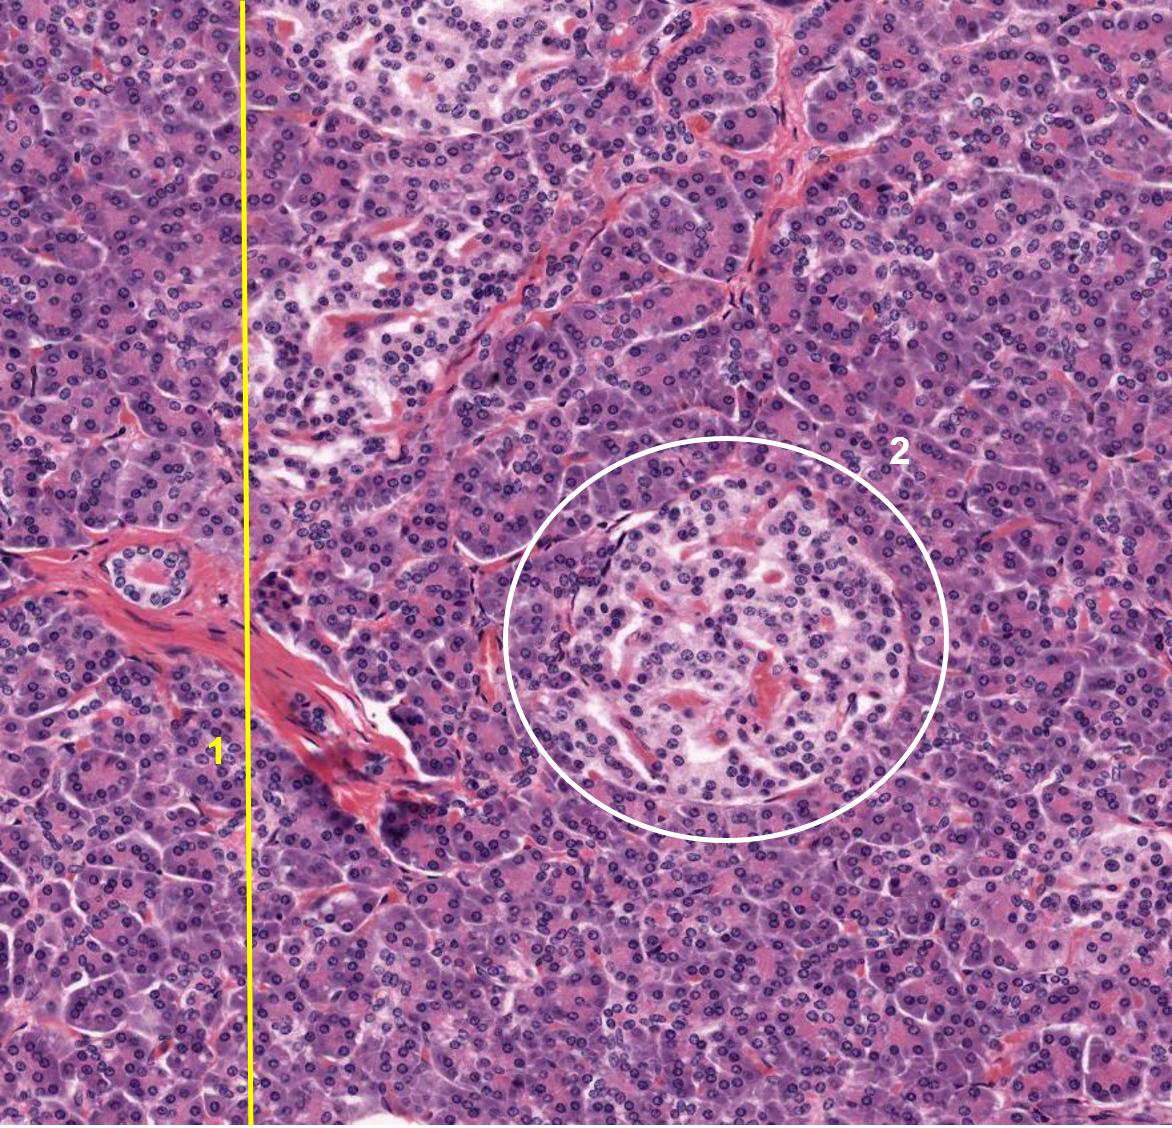

1: Pâncreas

2: Ilhota de Langerhans